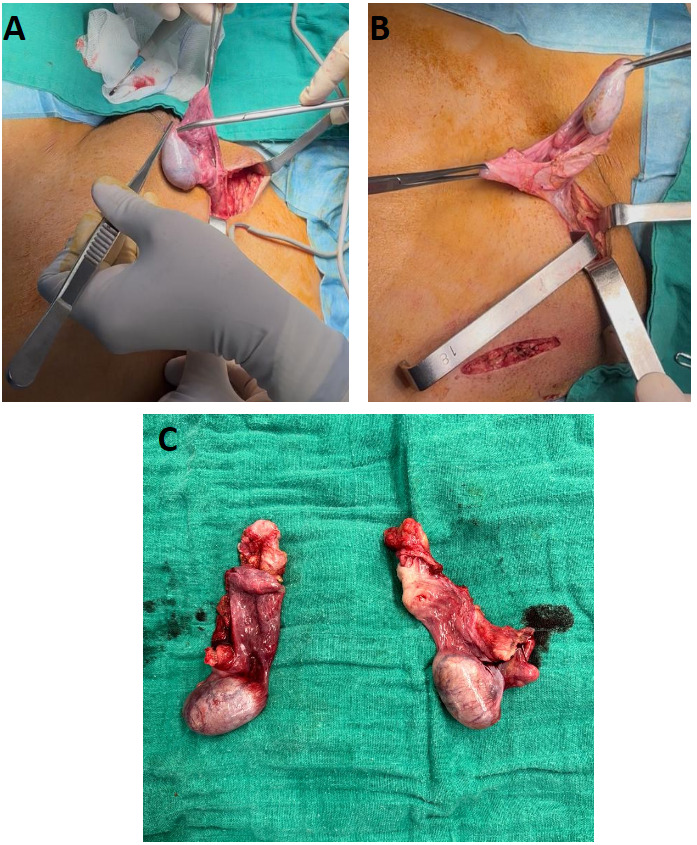

The patient underwent bilateral orchiectomy with McVay repair of the left inguinal hernia (Figure 3). Estrogen replacement therapy was initiated, and she performed vaginal dilation herself with guidance.

When chosen, bilateral gonadectomy is typically performed via minimally invasive/inguinal approaches with attention to hernia repair if indicated; outcomes are favorable in experienced centers.8